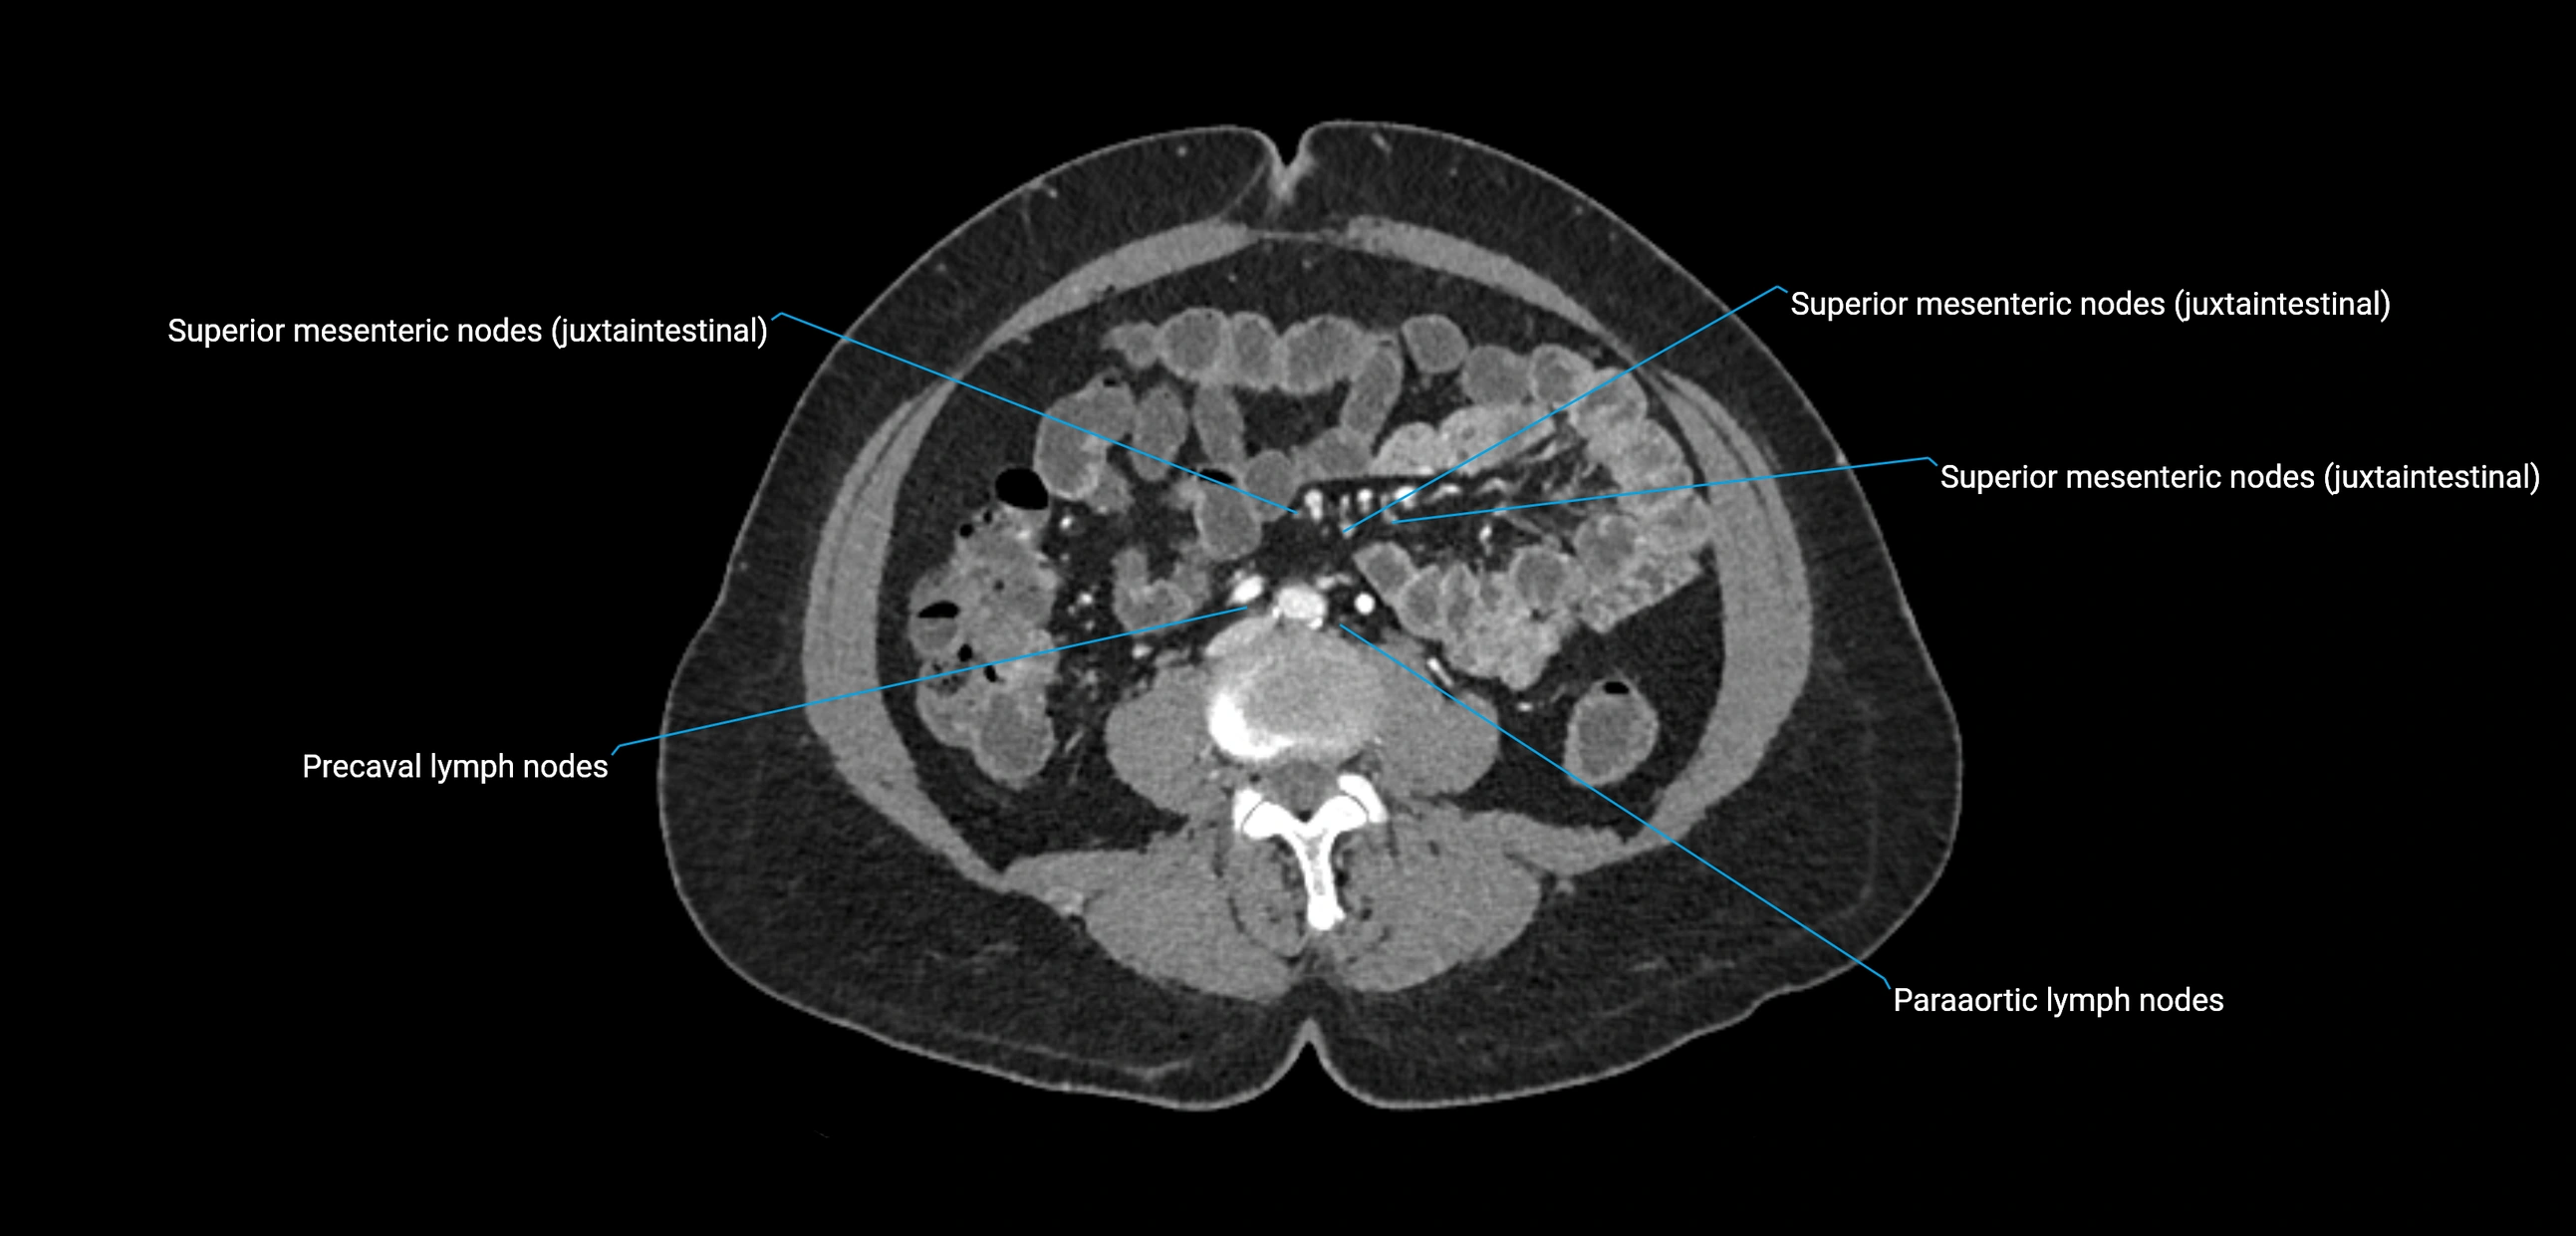

CT Appearance

CT Pre-Contrast:

• Nodes appear as soft-tissue density nodules adjacent to the aorta and IVC

• Calcification may be seen in chronic infections (e.g., tuberculosis)

CT Post-Contrast:

• Normal nodes enhance homogeneously

• Malignant nodes may show heterogeneous enhancement, central necrosis, or conglomerate formation

• Size >1 cm short axis is suspicious, though morphology and distribution are equally important

CT Venography (CTV):

• Demonstrates nodal encasement or compression of adjacent vessels (aorta, IVC, renal veins)

• Useful in staging testicular and ovarian malignancies

• Provides 3D reconstructions for retroperitoneal lymph node dissection planning

CT image

image